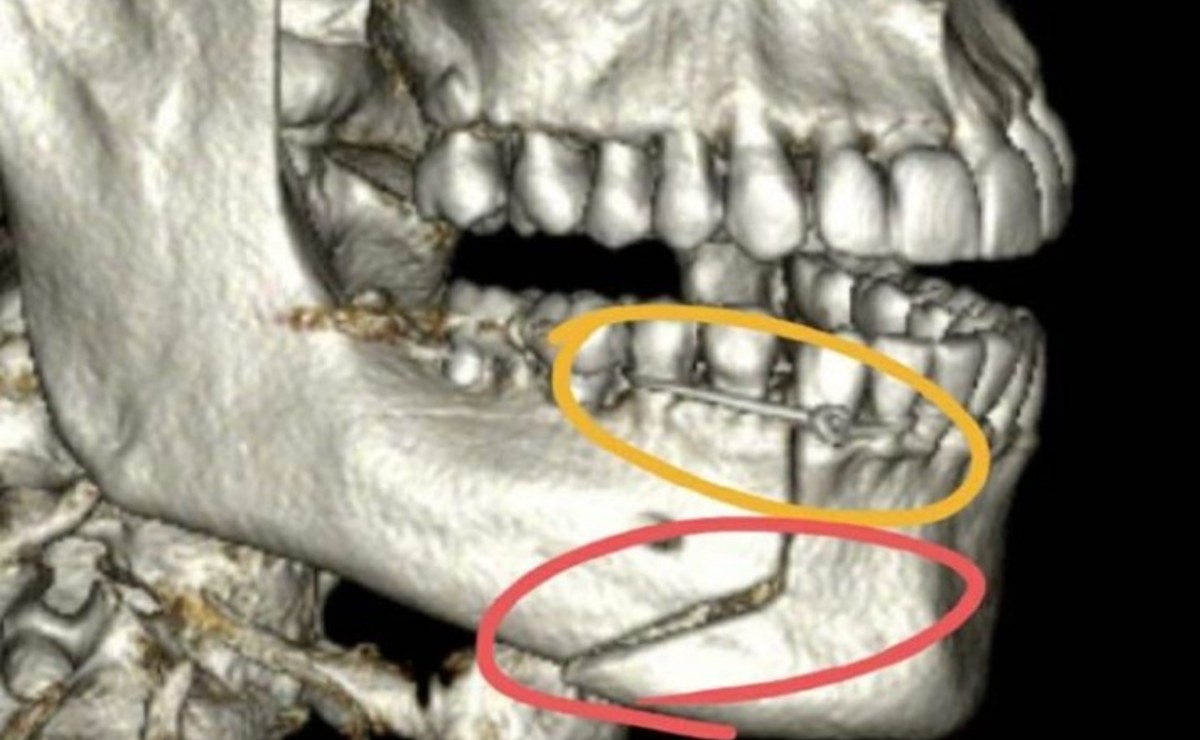

“O que aconteceu foi que eu estava com alguns amigos, e do nada eu fui puxado pelas costas, pelo pescoço, jogado no chão e fui agredido”, contou. “Vítima de socos e chutes que levaram a uma fratura exposta na minha mandíbula.”

Emocionado, ele disse que já havia percebido a gravidade da lesão no caminho do hospital. “A impressão que eu tinha era que minha boca estava pendurada naquele momento”, lembrou. “Liguei imediatamente para minha dentista, que me orientou a ir para um hospital mais próximo.”

Ele disse que a profissional acompanhou de forma virtual o atendimento da equipe médica local. “O médico e sua equipe que foram espetaculares, agradeço aqui publicamente”, disse. Ele explicou que a mandíbula dele foi amarrada com um fio de aço para que ele pudesse viajar para São Paulo, onde fez uma cirurgia para correção da mesma.

De volta a São Paulo no dia 7 de janeiro, ele fez a cirurgia no hospital Albert Einstein. “Naquele momento, eu só pensava na minha família, nos meus filhos, eu senti muito medo de ficar com sequelas para sempre, porque a minha boca ainda está torta e muito inchada e roxo”, afirmou.